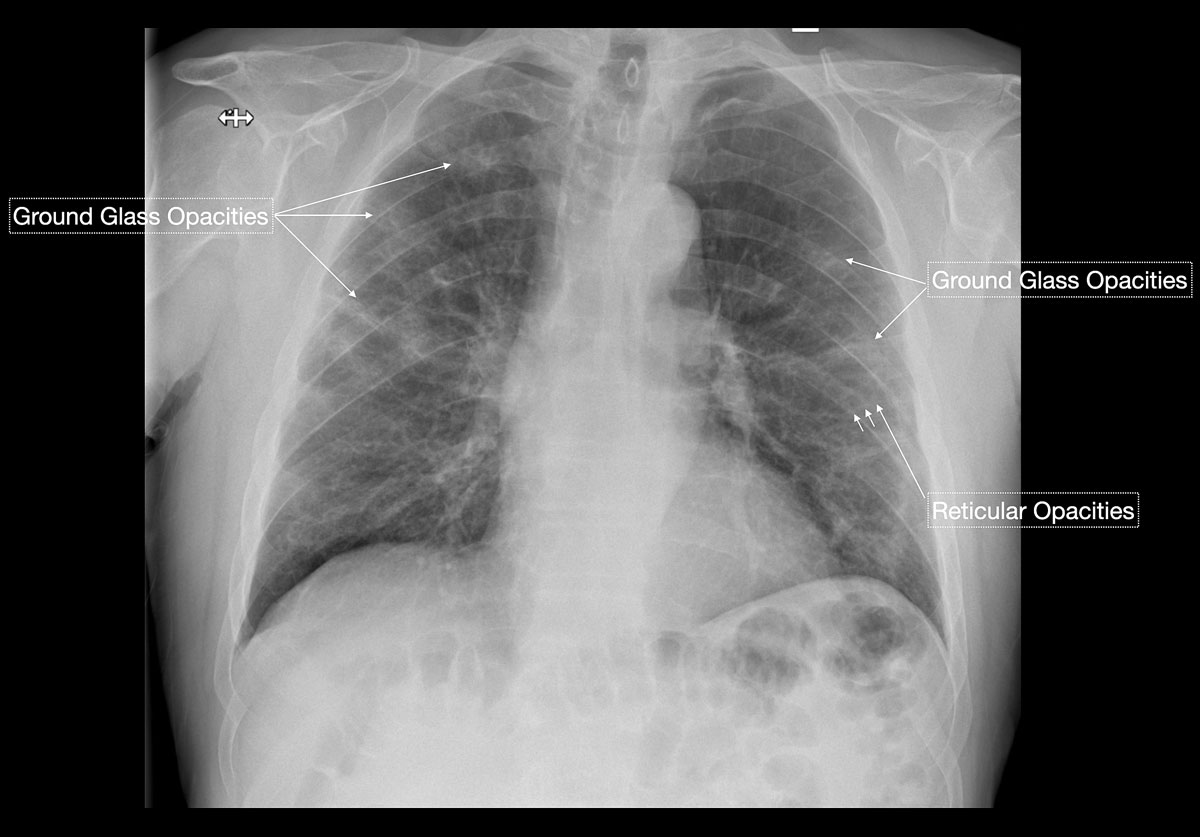

Figure 1 Schematic depiction of typical chest x-ray findings for COVID-19: bilateral, reticular and focal ground glass opacities or consolidative air space opacities in a peripheral and basal distribution. Earlier stage disease shows predominantly ground glass opacities; with progression pre-existing ground glass opacities transform into consolidative air space opacities.

Figure 2 A 71-year-old male patient with cough, intermittent fever and progressive dyspnoea. Early findings were predominantly peripheral ground glass opacities and reticular opacities. No consolidations or pleural effusions are seen. Subsequent nasopharyngeal RT-PCR test was positive for COVID-19.

Figure 4 A 31-year-old female patient working as a waitress presented with episodes of high fever and progressive shortness of breath. Chest x-ray, performed at the same time as nasopharyngeal RT-PCR testing, showed very subtle evidence of faint ground glass opacities and with a superimposed reticular pattern, which raised the high suspicion of an early stage COVID-19 infection. No consolidation or pleural effusions were evident. RT-PCR test results available after 48 hours confirmed COVID-19.